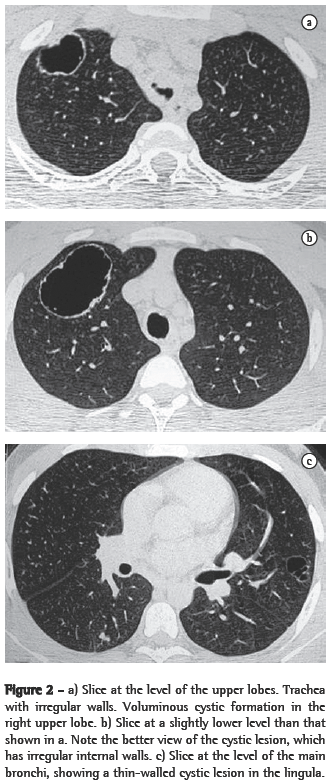

In all eight cases, the CT scans revealed polypoid formations in the trachea. In one case, injury to one of the main bronchi was identified. Seven patients presented involvement of the pulmonary parenchyma. In all eight cases, there were cavitated polypoid lesions, with irregular internal borders and walls of various thicknesses, multilobulated in six cases and presenting confluence of the lesions in five (Figures 1 through 5). Solid nodules were seen in six patients. An air-fluid level was observed in only one patient. The lesions were predominantly in the lung bases in three patients and in the middle thirds in two, whereas they were evenly distributed in two. In one patient, the lesions were accompanied by a mass, and, in another patient, they were accompanied by consolidation. In the latter case (Figure 5), there was malignant degeneration in multiple lesions. Signs of air trapping were also observed in one case. There were no identified instances of lymph node enlargement or pleural effusion.

Chest X-rays can occasionally produce findings suggestive of the disease, such as the combination of solid or cavitated pulmonary nodules and vegetative nodular lesions in the trachea or in the main bronchi. Unlike the pulmonary nodules, which are often identified on simple chest X-rays, intralumen papillomas in the trachea or bronchi are rarely visible on X-rays.(4) In practice, therefore, the disease is rarely diagnosed on the basis of chest X-ray findings. The nodules are typically multiple, well defined, of various dimensions, cavitated and thick-walled, being more numerous in the basal and posterior lung regions.(3,4) The cavitated nodules can be air-filled or, when infected, can present an air-fluid level.(4)

Chest X-rays are inferior to CT scans of the chest, especially those performed using spiral CT (volumetric acquisition), in the initial phases of pulmonary dissemination, due to the fact that CT better characterizes and allows better visualization of nodular tracheobronchial vegetation, Tomographic findings include focal or diffuse airway narrowing caused by the nodules. The nodules form on the mucosal surface, and their invasion into the lumen is best evaluated using CT.(3) These alterations are easily correlated with the disease when there is a clinical history of papillomatosis.(4) Other findings related to airway obstruction and accompanying infections are atelectasis, consolidations, air trapping and bronchiectasis.(2-4) In our sample, polypoid formations in the trachea were observed on all of the CT scans Seven patients presented involvement of the pulmonary parenchyma, characterized by cavitated polypoid lesions with irregular internal borders and walls of various thicknesses, with a multilobulated aspect and a tendency toward confluence. Solid nodules were seen in six patients. None of the patients presented lymph node enlargement or pleural effusion.